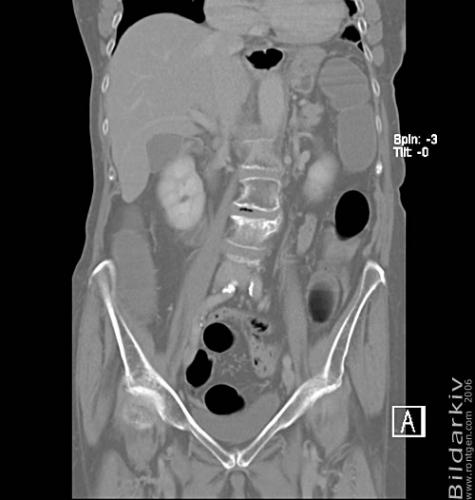

CT colon 27

Datortomografi av tjocktarmen (colon) med infunderad luft i tarmen samt med kontrast i blodbanan. Koronar bildserie.

CT multislice 16